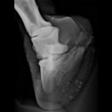

Silvas hov operation (keratom) - Røtgenbillede af keratomet (hornsøjlen) billede 1